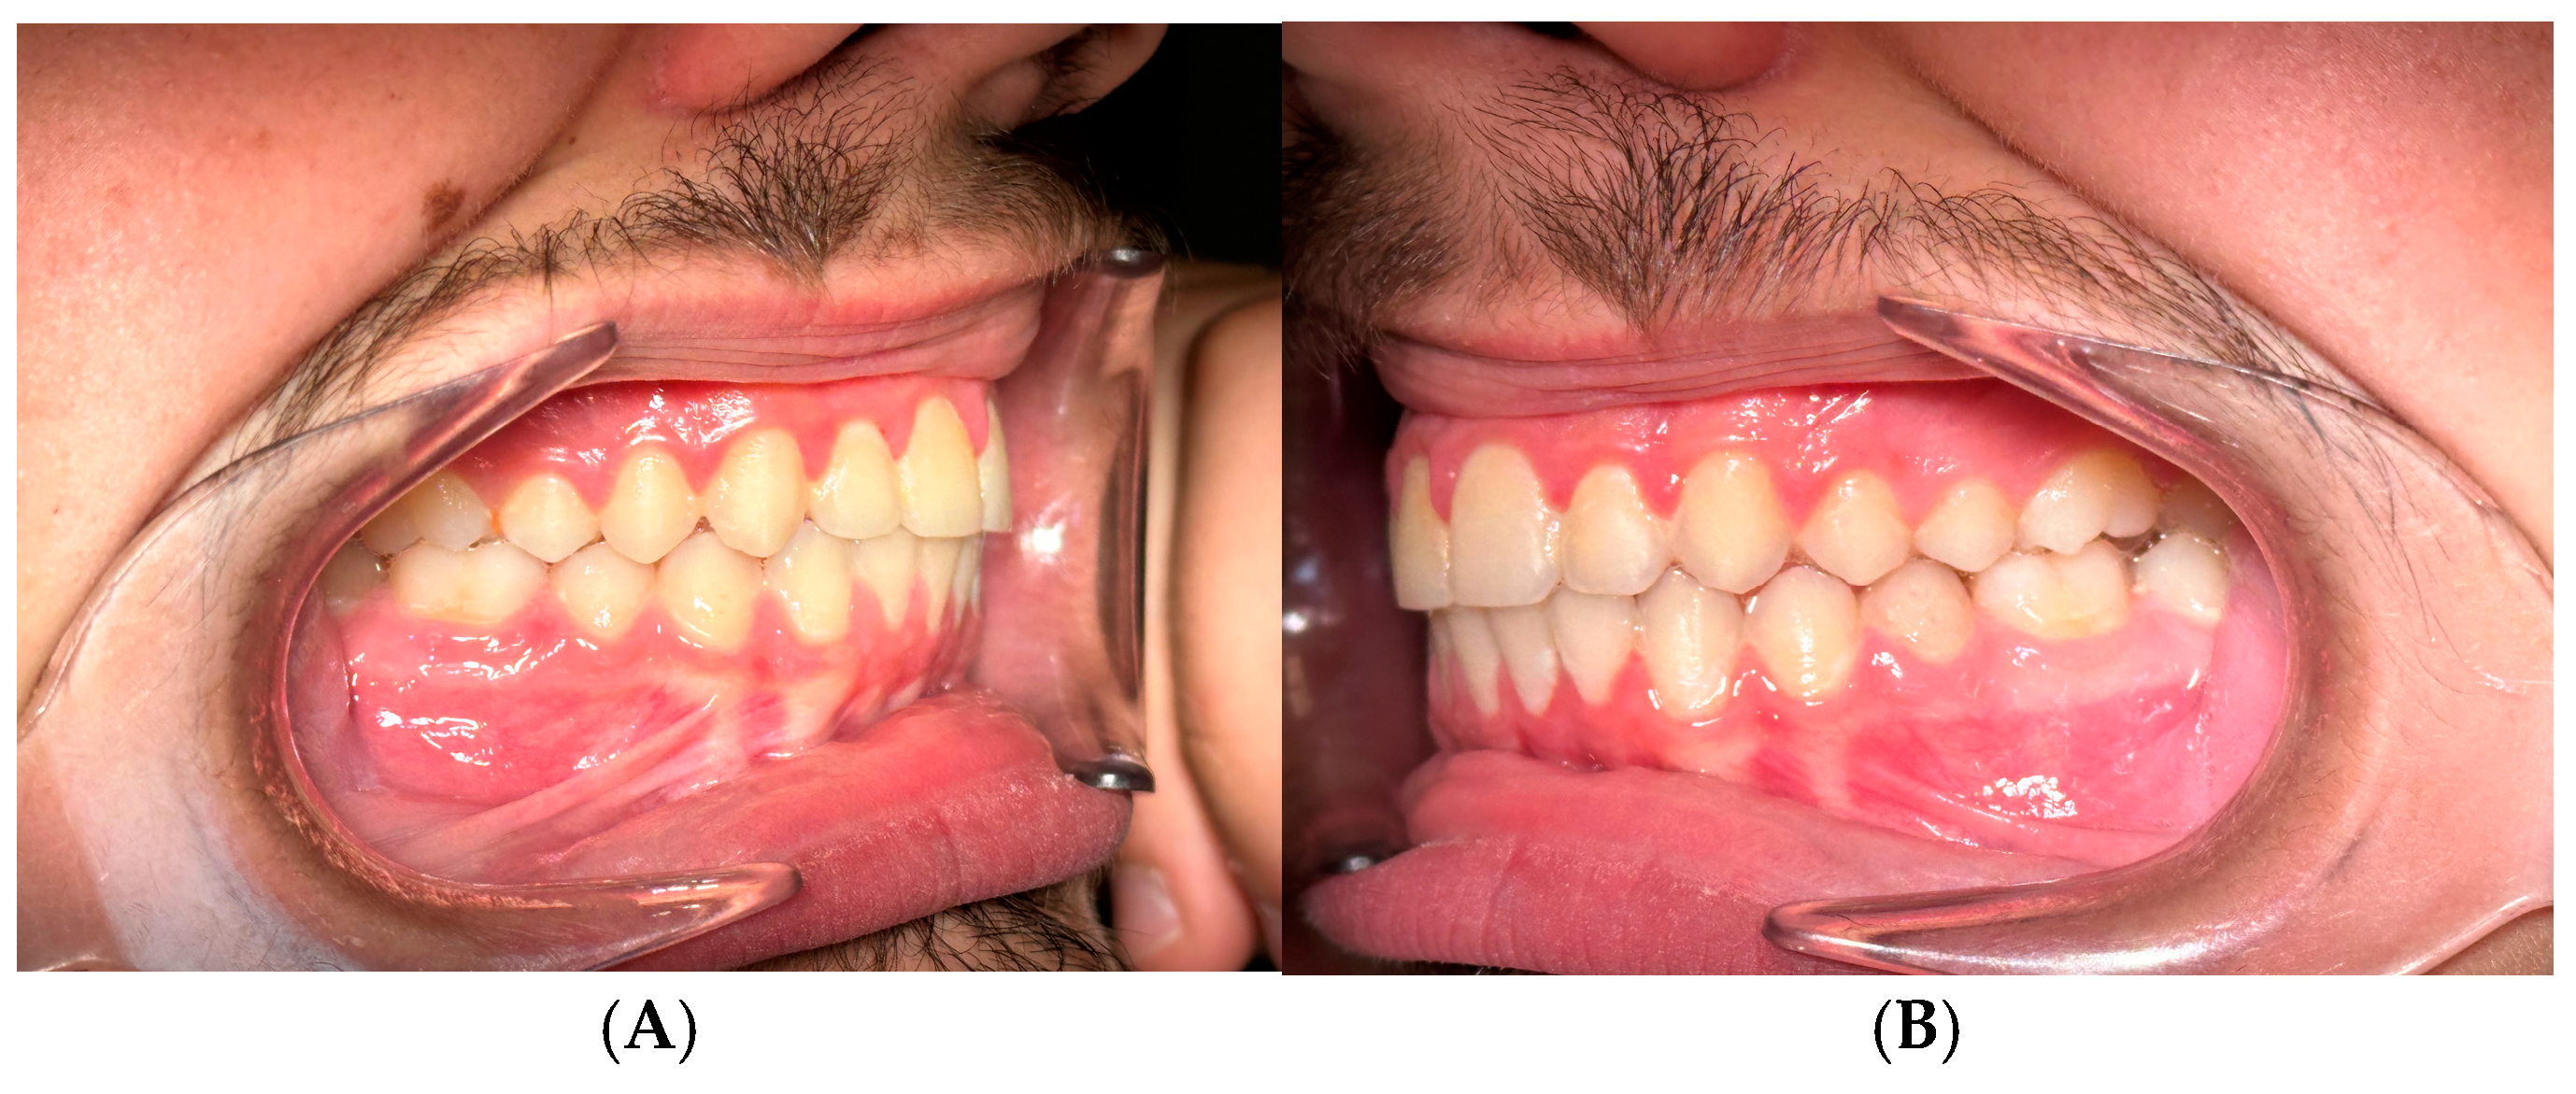

The increased overjet (compared to what is usually brought to 0 mm) allows for faster achievement of intercuspation. After a week the overjet will have increased and will allow the intercuspation of the posterior teeth. In this period of time the dentoskeletal system and the neuromuscular system undergo adaptive phenomena that allow the dental arches to return to contact. Even with this modification to the classic protocol, there is the possibility of reactivating the device weeks later, when normally there is a mild recurrence (1-2 mm) of class II. So since it does not affect this aspect, our goal is to obtain molar intercuspation as quickly as possible which would be much slower with overjet brought to 0 mm. Therefore, after approximately 1 week the patient presents an occlusion of numerous teeth in contact with maximum intercuspation. This phase of muscular and joint adaptation is clinically visible in the photos of the patients as soon as the device is cemented in the mouth and subsequently at the check-up after 7 days: initially the muscles appear "forced" to maintain the protruded position (an aspect common to many functional devices including the Frankel), while the muscular posture improves significantly already after a week when intercuspation has been obtained (

Figure 4 A,B,C).